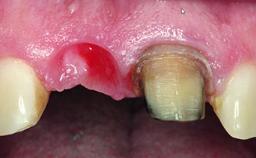

A 28-year-old patient presented at her general dentist’s office and complained about the appearance of her tooth 21. The patient had a history of trauma to this tooth. Endodontic treatment had been performed in the past and a crown placed on the tooth. A procedure to replace the old crown was performed by her dentist; however, a perforation on the middle third of the root occurred, and extraction of tooth 21 was suggested. Upon clinical and radiographic examination of the patient, who had been referred to us, replacement of tooth 21 by a dental implant appeared to be indicated.

Placement Protocol Early or late implant placement

Bone Volume Deficient horizontally, allowing simultaneous augumentation

Esthetic Risk High